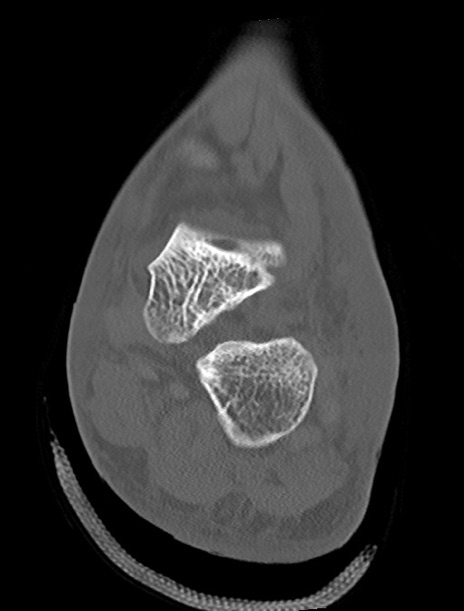

左足関節CT

横断像